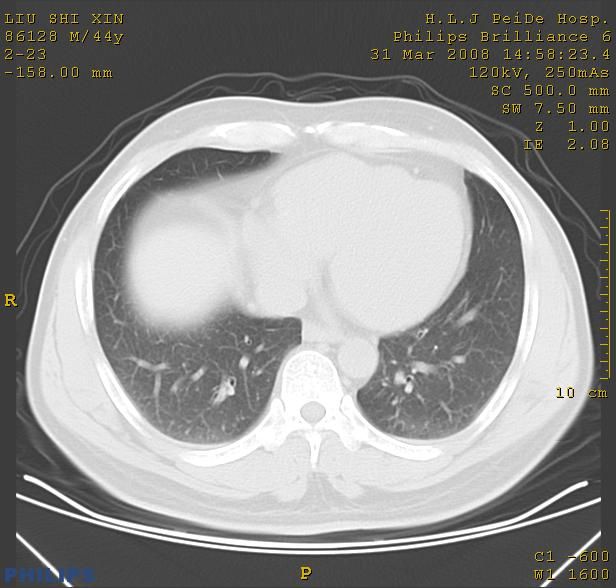

标题: CT13096:请分析胸膜下结节的影像基础是什么 有病理结果 [打印本页]

标题: CT13096:请分析胸膜下结节的影像基础是什么 有病理结果

中心型肺癌并阻塞性肺炎、两肺及胸膜多发转移。

右上肺及胸膜下结节影均考虑结核可能性大,建议上传纵隔窗.

结节灶与血管末梢相通象转移灶;小三角状尖部有纤维索是胸膜拉扯征;纵隔旁大片实性影有点状钙化;周围有名显纤维瘢痕征可考虑瘢痕癌

胸膜下结节是转移了。

本病例有病理结果是,鳞状上皮癌,胸膜下结节影病现诊断的肿大淋巴结,谢谢大家分析,请问胸膜下结节是肿大淋巴结怎么解释